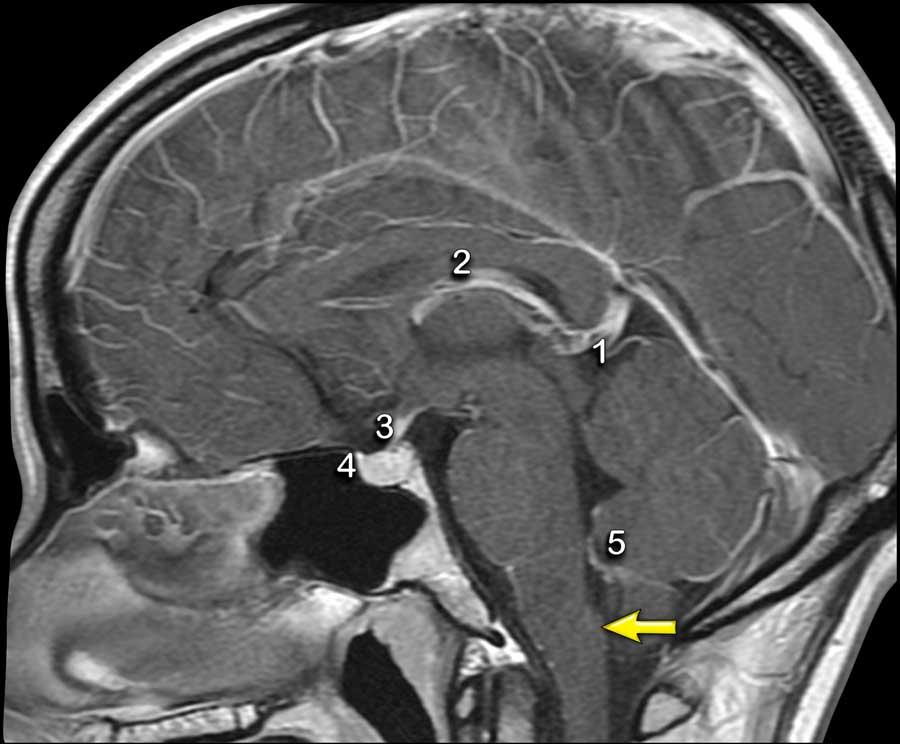

Ngấm thuốc bình thường

Các cấu trúc trong não không có hàng rào máu-não hoặc các cấu trúc ngoài trục sẽ có hiện tượng ngấm thuốc bình thường.

Các cấu trúc này bao gồm màng cứng, tuyến tùng (1), mạch máu (2), cuống tuyến yên (3) và tuyến yên (4), đám rối mạch mạc (5) và vùng postrema (mũi tên).

Vùng postrema là một cấu trúc đôi có mạch máu phong phú nằm ở hành não trong thân não, được định vị ngay phía dưới-sau của sàn não thất bốn.